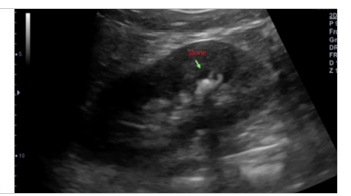

Figure 2: Increased Transplanted Kidney Volume of 7 Years’ Transplantation Duration in A 37-Year-Old Male